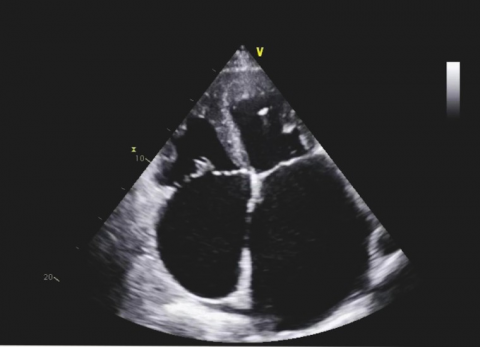

Wideo Echokardiografia. Przypadek 24

prof. dr hab. n. med. Olga TrojnarskaPacjent z niewydolnością serca NYHA II/III, po przebytym zawale serca.